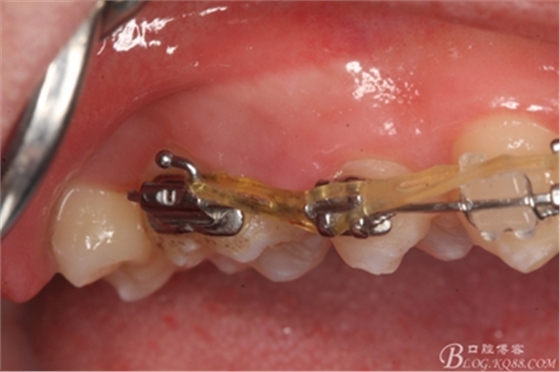

圖1.術(shù)前患者的口內(nèi)照片:16與14之間有約2mm間隙,矯治器已經(jīng)安裝到位。